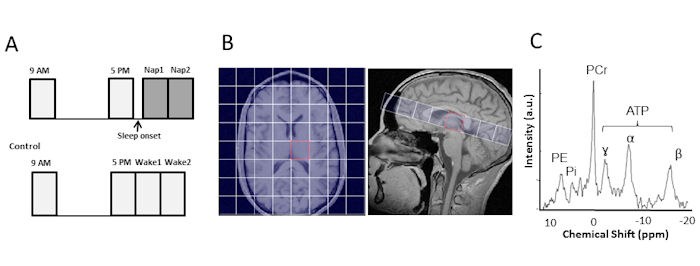

In einer longitudinalen Studie wurden gesunde Probanden morgens, spätnachmittags und während eines kurzen Mittagsschlafes untersucht (Abb. 1).

Abb. 1:

A. 30 gesunde Probanden wurden in zwei Messsitzungen am gleichen Tag, morgens um 9:00 sowie am Spätnachmittag um 17:00, untersucht. Im Anschluss an die Nachmittagsmessung wurden 15 Probanden während eines Mittagsschlafes gemessen.

B. Sagittale und axiale Schnittebenen überlagert von einem CSI 8 × 8 Voxelgrid (linke Hemisphäre ist auf der rechten Bildseite dargestellt).

C. 31- Spektrum des Voxels im linken Thalamus.